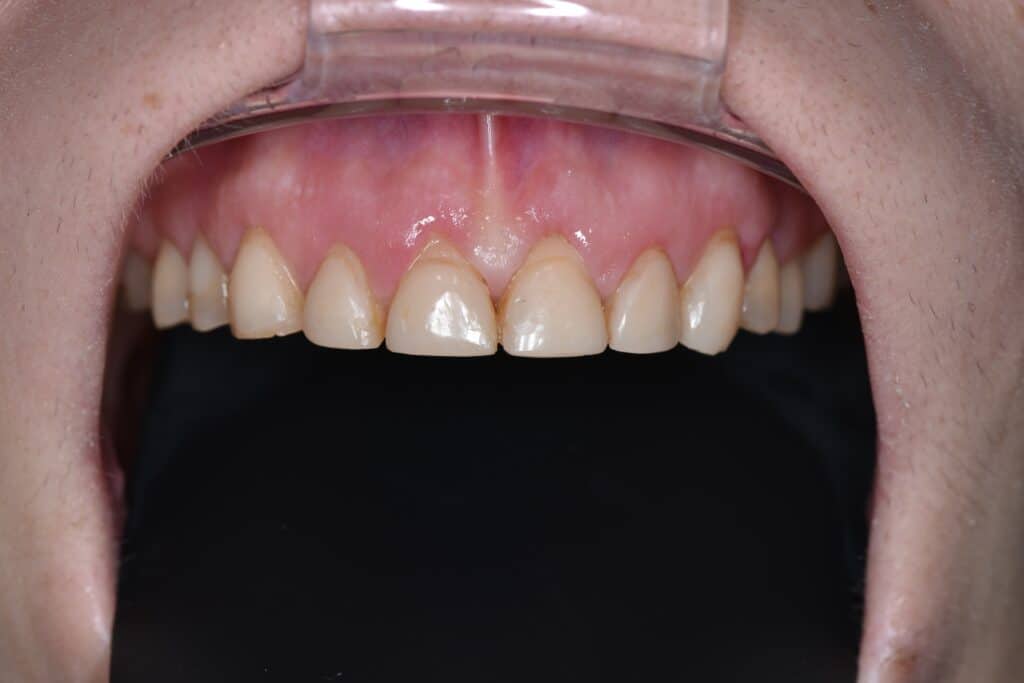

Die 38-jährige Patientin der Praxis Dr. Marius Bancila in München beklagte die unbefriedigende Ästhetik ihres Lächelns aufgrund der über die Jahre kurz gewor-denen, stark abradierten Zähne (Abb. 1).

Die Knirscherschiene, die sie zum Schutz

der Zahnsubstanz erhalten hatte, hatte sie kaum getragen. In der aktuellen Situation hatte die Patientin keine Schmerzen, war aber mit dem Erscheinungsbild ihres Lächelns sehr unzufrieden. Ihre allgemeine Anamnese war unauffällig. Der klinische Befund bestätigte, dass die Zähne im Ober- und Unterkiefer, besonders die Frontzähne des Oberkiefers, von starken Abrasionen betroffen waren. Darüber hinaus ergab der klinische Befund bei inkomplettem Zahndurchbruch und ske-lettaler Klasse Il zusätzlich Verfärbungen der Zahnsubstanz und Gingiva-Rezessio-nen (Abb. 2 und 3).